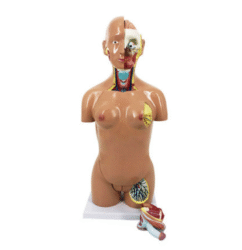

ATL-108 CENTRAL VENOUS PUNCTURE SIMULATOR SOFT

This model is divided into internal carotid artery, carotid artery, subclavian vein and femoral vein and main arteries of femoral artery. Can be used for the injection of internal jugular vein, collarbone vein and femoral vein, blood and other targeted training and the practice of long catheter intubation. This model only can simulate the pulse of carotid artery, and femoral artery, but also can locate veins.

Packing: 1pcs/carton, 92x51x23cm, 10.5kgs